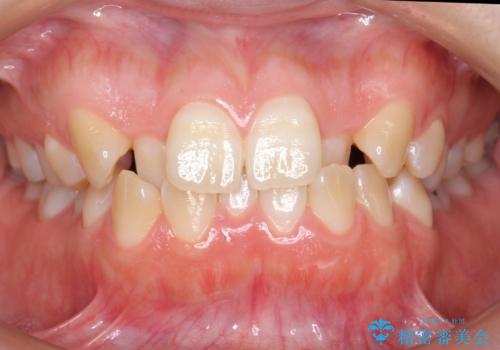

ワイヤーによる抜歯矯正でガタガタと深いかみ合わせの改善